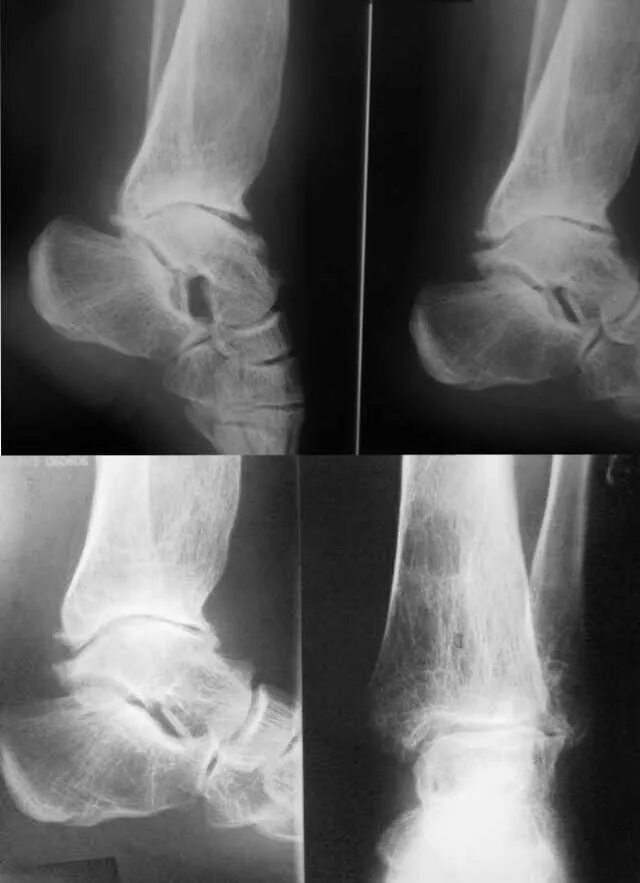

Перелом вывих голеностопного сустава